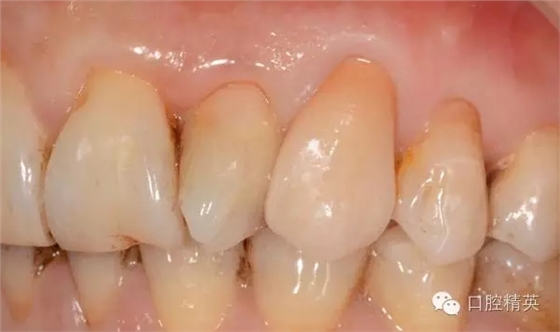

圖12修復(fù)體代入口內(nèi)正面照

一. 23根管治療后樁冠修復(fù)(纖維樁+氧化鋯全瓷冠修復(fù))

二. 11.12.13.樹脂修復(fù)